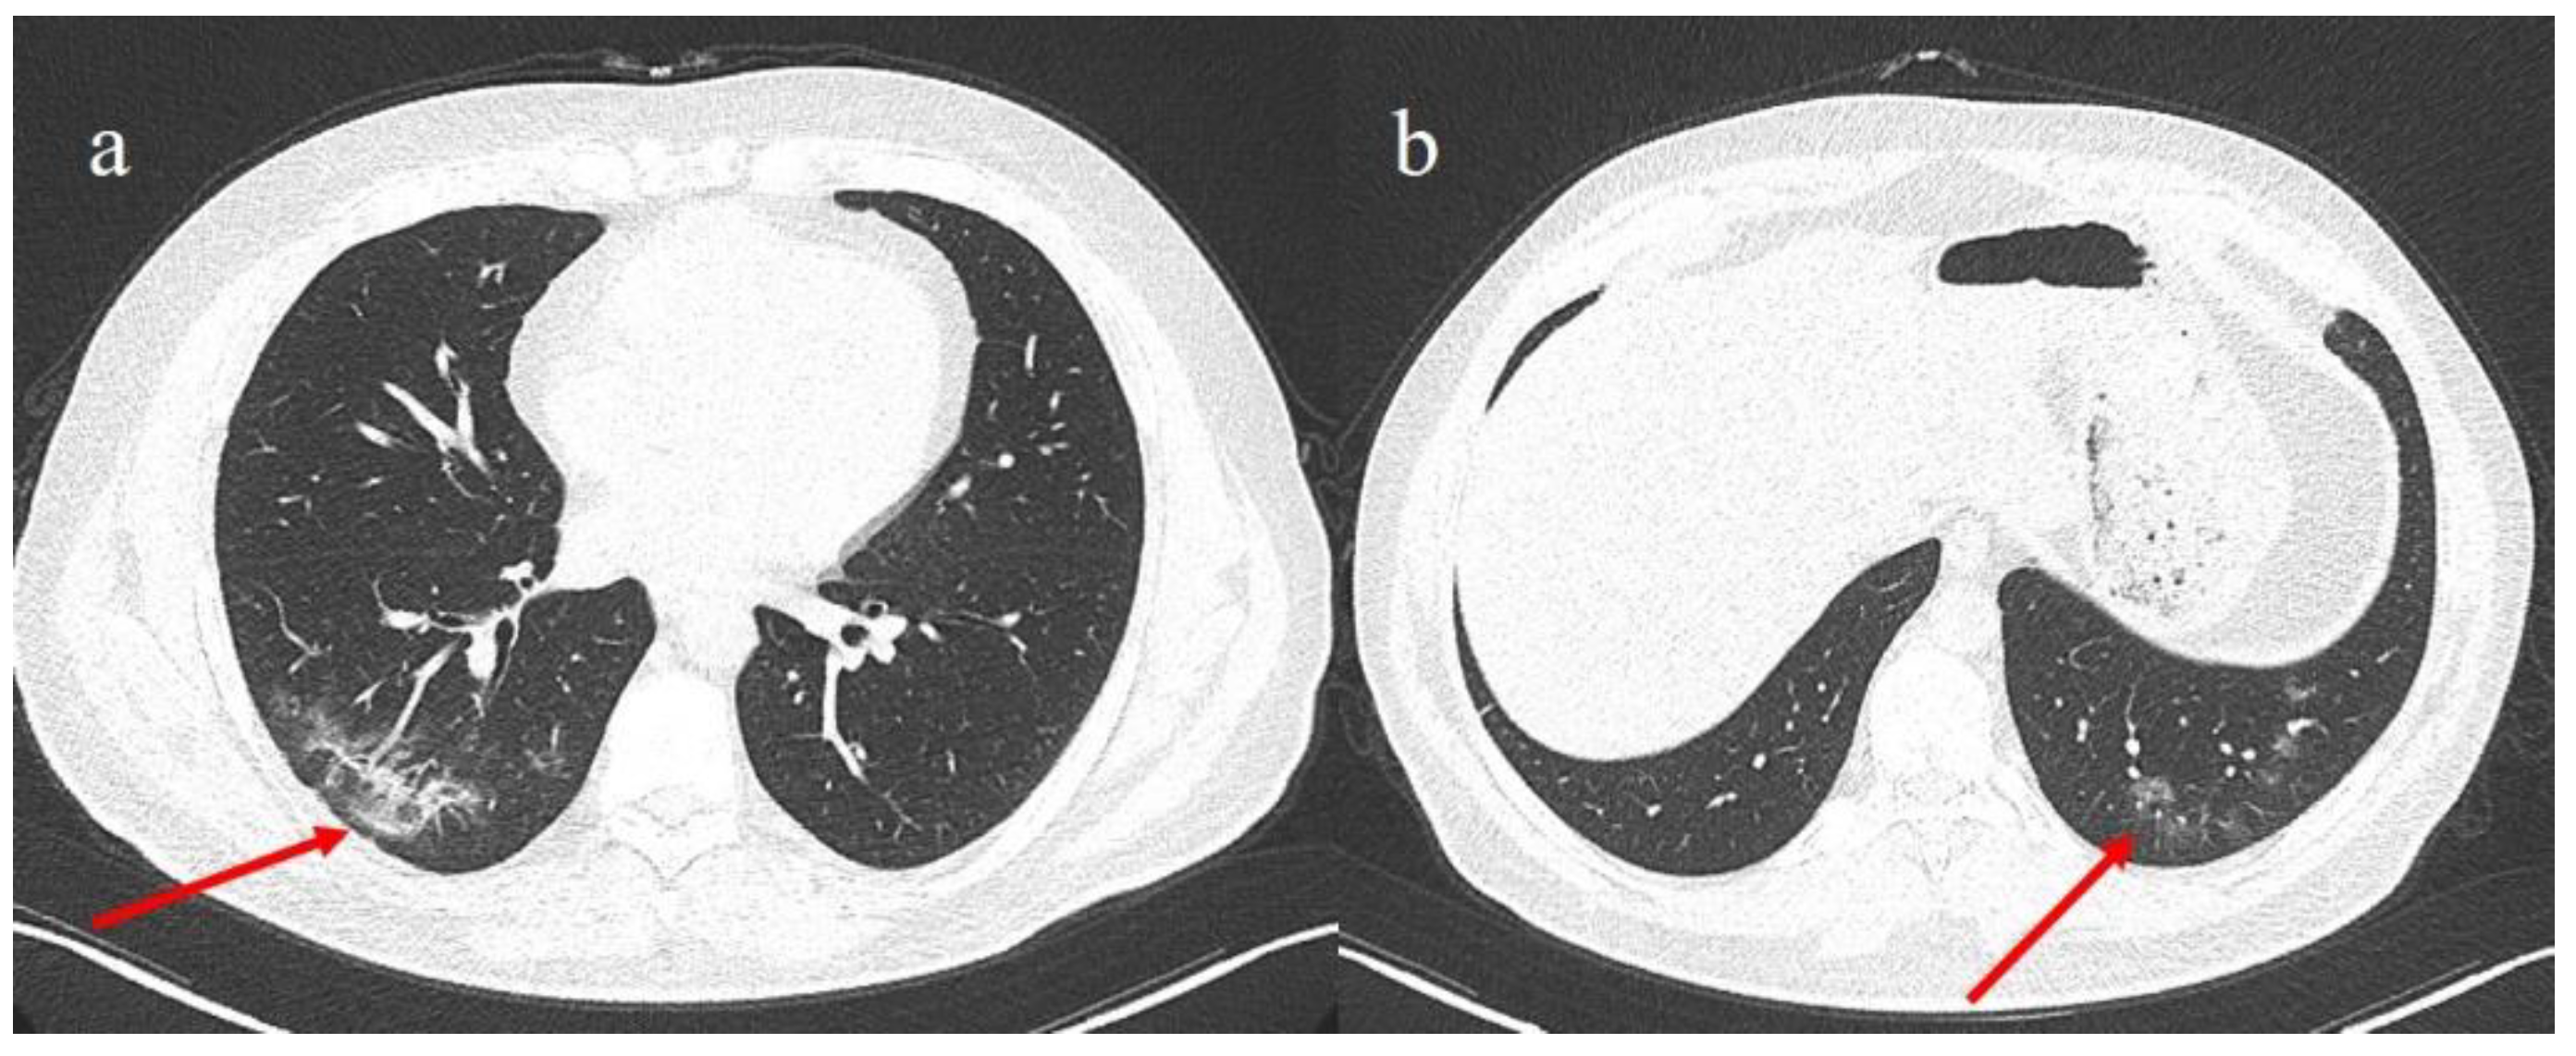

- Brogna, B.; Bignardi, E.; Brogna, C.; Alberigo, M.; Grappone, M.; Musto, L.; Megliola, A.; Salvatore, P.; Fontanella, G. Typical CT findings of COVID-19 pneumonia in patients presenting with repetitive negative RT-PCR. Radiography 2020. [Google Scholar] [CrossRef]